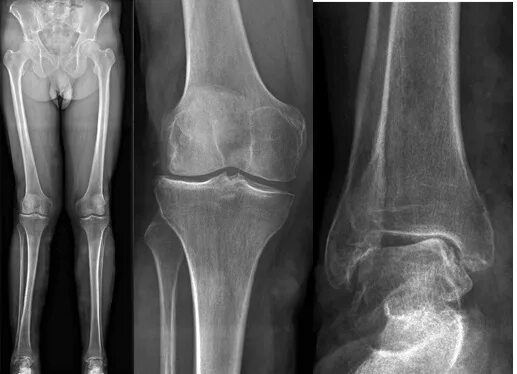

Вальгусная деформация коленных суставов у взрослых